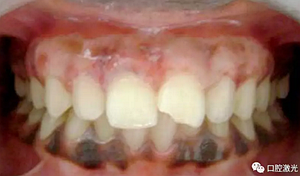

術(shù)后即刻

患者術(shù)后無明顯疼痛不適,沒有出現(xiàn)大量出血、感染或結(jié)痂現(xiàn)象。整個(gè)恢復(fù)過程較為順利?;颊呓邮芏雀?,治療效果明顯。

術(shù)后一周

術(shù)后三月